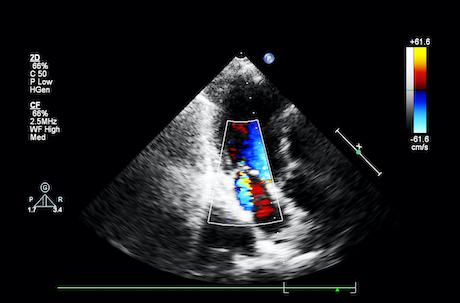

Bioprothèse